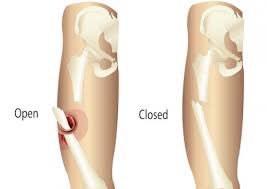

-عن طريق علاقة الكسر مع ال Enviroment

ممكن كسر مفتوح كسر اخترق الجلد او العظم اخترق الجلد نسميه اوبن .

او closed داخل الجلد .